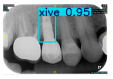

However, since the implant launched onto the market, dental treatment related to implant issues has become the everyday practice of dentists’ lives in clinics [10]. The design of the implants, from shape to surface coating, is different from brand to brand [11]. But it is inevitable to come into implant complications [12,13], such as screw fracture, healing abutment loss, etc., whether the clinician itself treats the implant or implant prosthesis. Different surface coatings [14,15] and threads of the implant design [16,17] may be easily identified in vitro. Moreover, once the implants are in vivo, the clinicians can only identify implant brands through radiography or the clinicians’ familiarity with the implant. If the clinicians are not familiar with the brands, then it is hard to tell which brand the implant is from in vivo. As the number of implant brands on the global market grows, it has become increasingly complex for clinicians to identify and familiarize themselves with all available implant systems accurately. 3i and Xive are two of the most widely used and clinically validated implant brands worldwide, with excellent long-term success rates [18] and reliable implant-abutment connection designs [19]. Therefore, we strategically focused on 3i and Xive implants in this study to ensure clinical relevance and practical significance. Concentrating on these two brands allows our model to address many real-world clinical cases and enhances its applicability in everyday dental practice. Clinicians will likely encounter both implant brands due to their widespread use in global dental clinics [20]. Moreover, as the implant’s screwdrivers differ from brand to brand, the identification of implant brands is very important to clinicians and patients. The marginal accuracy of the implant-abutment connection may vary due to misidentification and lead to unknown clinical problems [21,22]. The PA imaging results of two implant brands of different types at different resolutions (R) are shown in Figure 1. These two commonly used implant brands exhibit highly similar characteristics, with the most apparent difference being the variation in implant threading patterns. However, this distinction is not easily discernible for PA datasets.

Figure 1.

Imaging of two implant brands at different resolutions.